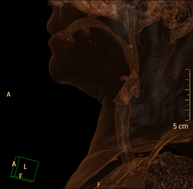

- TC Cuello

Prueba radiológica que consiste en obtener imágenes del cuello de alta definición anatómica mediante el empleo de un equipo de TC (Tomografía Computarizada). Indicaciones: estudio de tiroides, control de tumores tratados, estudio de ganglios, infecciones y abscesos.

- TC Laringe

Prueba radiológica que consiste en obtener imágenes de la laringe de alta definición anatómica mediante el empleo de un equipo de TC (Tomografía Computarizada). Indicaciones: afonía súbita o crónica, dificultad respiratoria.